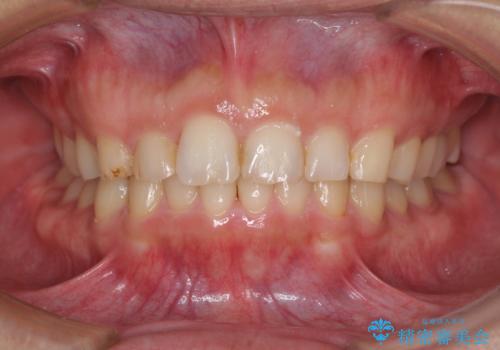

[インビザライン ライト] 短期間(3.5ヶ月)で終わるマウスピース矯正

![[インビザライン ライト] 短期間(3.5ヶ月)で終わるマウスピース矯正の症例 治療後](https://seimitsushinbi.jp/wp/wp-content/uploads/2020/02/2f36cdf472a802b537022ae239b8cb6b-500x350.jpg?v=1580813669)